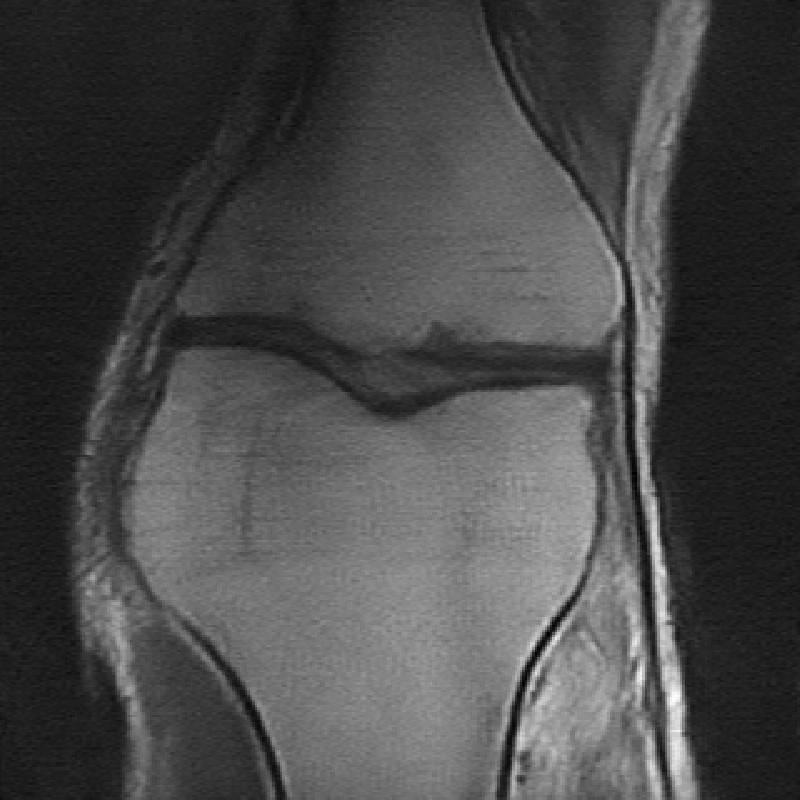

The data used in the undersampled MRI experiments were obtained from the NYU fastMRI Initiative [45]. The primary goal of the fastMRI dataset is to test whether machine learning can aid in the reconstruction of medical images. We trained and tested on a subset of the single-coil knee dataset, which consist of simulated single-coil measurements. In all tests, we use complex-valued data, which interfaces with our deep networks by treating the real and imaginary parts of the images as separate channels. We measure reconstruction accuracy with respect to the center 320320 pixels of the complex IFFT of the fully-sampled k-space data. For the purpose of visualization, we display only the magnitude images in the following sections.

In Table 1 we present our main results. We present sample reconstructions for the deblurring problem and MRI reconstruction problem in Figs. 7 and 8. For reference, the ground truth, inputs to the networks, a total variation regularized reconstruction, and a RED reconstruction are presented in Figs. 5 and 6. We also provide in the Appendix a table of SSIM values as well as the full version of Table 1, which contains the standard deviations of PSNR.

While the magnitude of the improvements vary across domains and problems, we find that retraining the network with the proposed model adaptation techniques significantly improve performance by several dBs in the new setting. This effect is particularly striking in the case of MRI reconstruction with MoDL, where the βnaiveβ approach of replacing with in the network gives catastrophic results (a roughly 9 dB drop in reconstruction PSNR), while the proposed model adaptation approaches give reconstruction PSNRs within 1-2 dB of the baseline approach of training and testing with the same forward model in the case where is known.